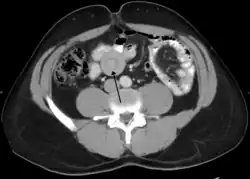

An intussusception as seen on CT

Small intestinal invagination on computed tomography

An intussusception is often suspected based on history and physical exam, including observation of Dance's sign. A digital rectal examination is particularly helpful in children, as part of the intussusceptum may be felt by the finger. A definite diagnosis often requires confirmation by diagnostic imaging modalities. Ultrasound is the imaging modality of choice for diagnosis and exclusion of intussusception, due to its high accuracy and lack of radiation. The appearance of target sign (also called "doughnut sign" on a sonograph, usually around 3 cm in diameter, confirms the diagnosis. The image seen on transverse sonography or computed tomography is that of a doughnut shape, created by the hyperechoic central core of bowel and mesentery surrounded by the hypoechoic outer edematous bowel.[10] In longitudinal imaging, intussusception resembles a sandwich.[10] It is also called "pseudokidney" sign because hyperechoic tubular centre is covered by a hypoechoic rim producing a kidney-like appearance.[11]